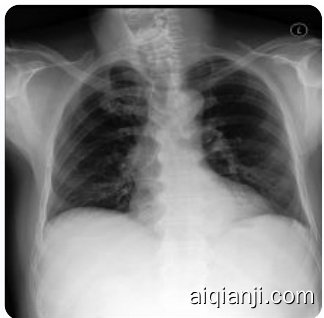

Instructions: You are a helpful radiology assistant. Describe what lines, tubes, and devices are present and each of their locations. Describe if pneumothorax is present; if present, describe size on each side. Describe if pleural eŦusion is present; if present, describe amount on each side. Describe if lung opacity (at elect as is, ůbrosis, consolidation, inůltrate, lung mass, pneumonia, pulmonary edema) is present; if present, describe kinds and locations. Describe the cardiac silhoueŵe size. Describe the width and contours of the media st in um. Describe if hilar enlargement is present; if enlarged, describe side. Describe what fractures or other skeletal abnormalities are present.

Given the PA view X-ray image . Reason for the study: History m with malaise pneumonia. Q: Describe the ůndings in the image following the instructions. A:

Figure 2 | Illustration of instruction task prompting with one-shot exemplar. (top) shows the task prompt for the chest X-ray report generation task. It consists of task-specific instructions, a text-only “one-shot exemplar” (omitting the corresponding image but preserving the target answer), and the actual question. The X-ray image is embedded and interleaved with textual context including view orientation and reason for the study in addition to the question. (bottom) shows the task prompt for the dermatology classification task. We formulate the skin lesion classification task as a multiple choice question answering task with all the class labels provided as individual answer options. Similar to the chest X-ray report generation task, skin lesion image tokens are interleaved with the patient clinical history as additional context to the question. The blue denotes the position in the prompt where the image tokens are embedded.

图 2 | 单样本示例的指令任务提示示意图。(top) 展示了胸部X光报告生成任务的任务提示。它包含任务特定指令、纯文本的"单样本示例"(省略对应图像但保留目标答案)以及实际问题。X光图像被嵌入,并与包含视图方向和检查原因等文本上下文交错排列。(bottom) 展示了皮肤病分类任务的任务提示。我们将皮肤病变分类任务设计为多选题形式,所有类别标签都作为独立选项提供。与胸部X光报告生成任务类似,皮肤病变图像token与患者临床病史交错排列,作为问题的附加上下文。蓝色表示提示中嵌入图像token的位置。